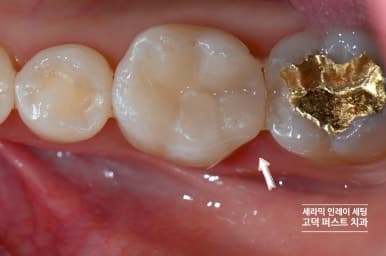

새 세라믹 인레이 장착 완료

스캔 데이터로 제작된 세라믹 인레이를 장착합니다. 경계면이 치아에 완벽하게 밀착되어 재발 위험이 최소화됩니다.

치료 후 엑스레이 확인

치료 후 엑스레이에서 인레이 변연부가 치아에 완전히 적합된 것이 확인됩니다. 틈새 없이 밀착되어 있습니다.